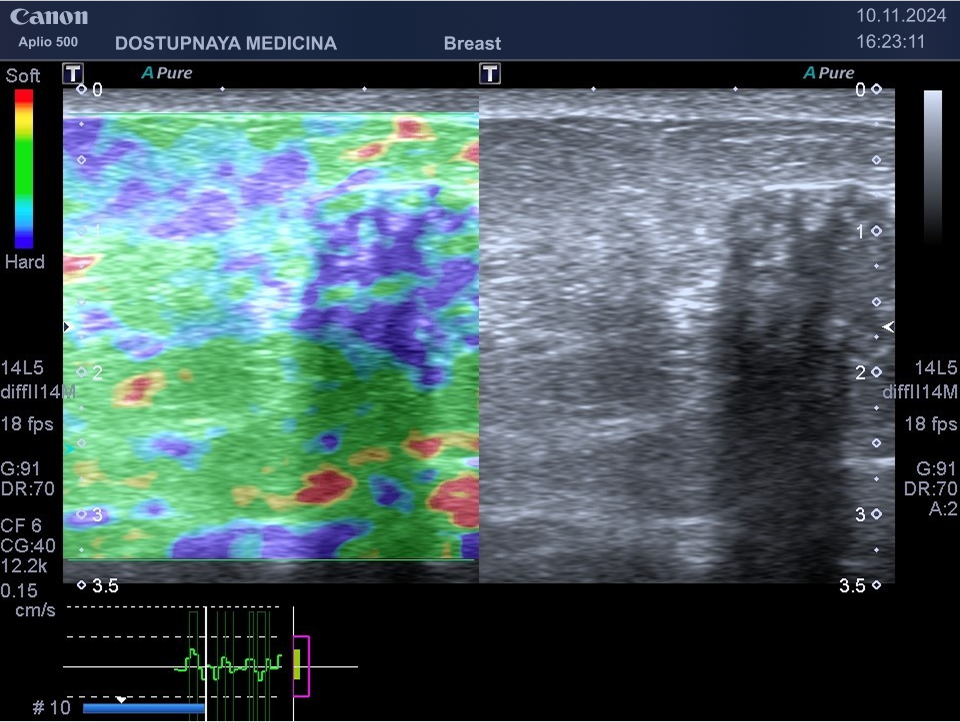

При ультразвуковом исследовании в кисте может быть визуализирован папиллярный компонент с кровотоком в режиме ЦДК. Так могут выглядеть цистаденопапилломы, которые считаются аблигатным предраком.